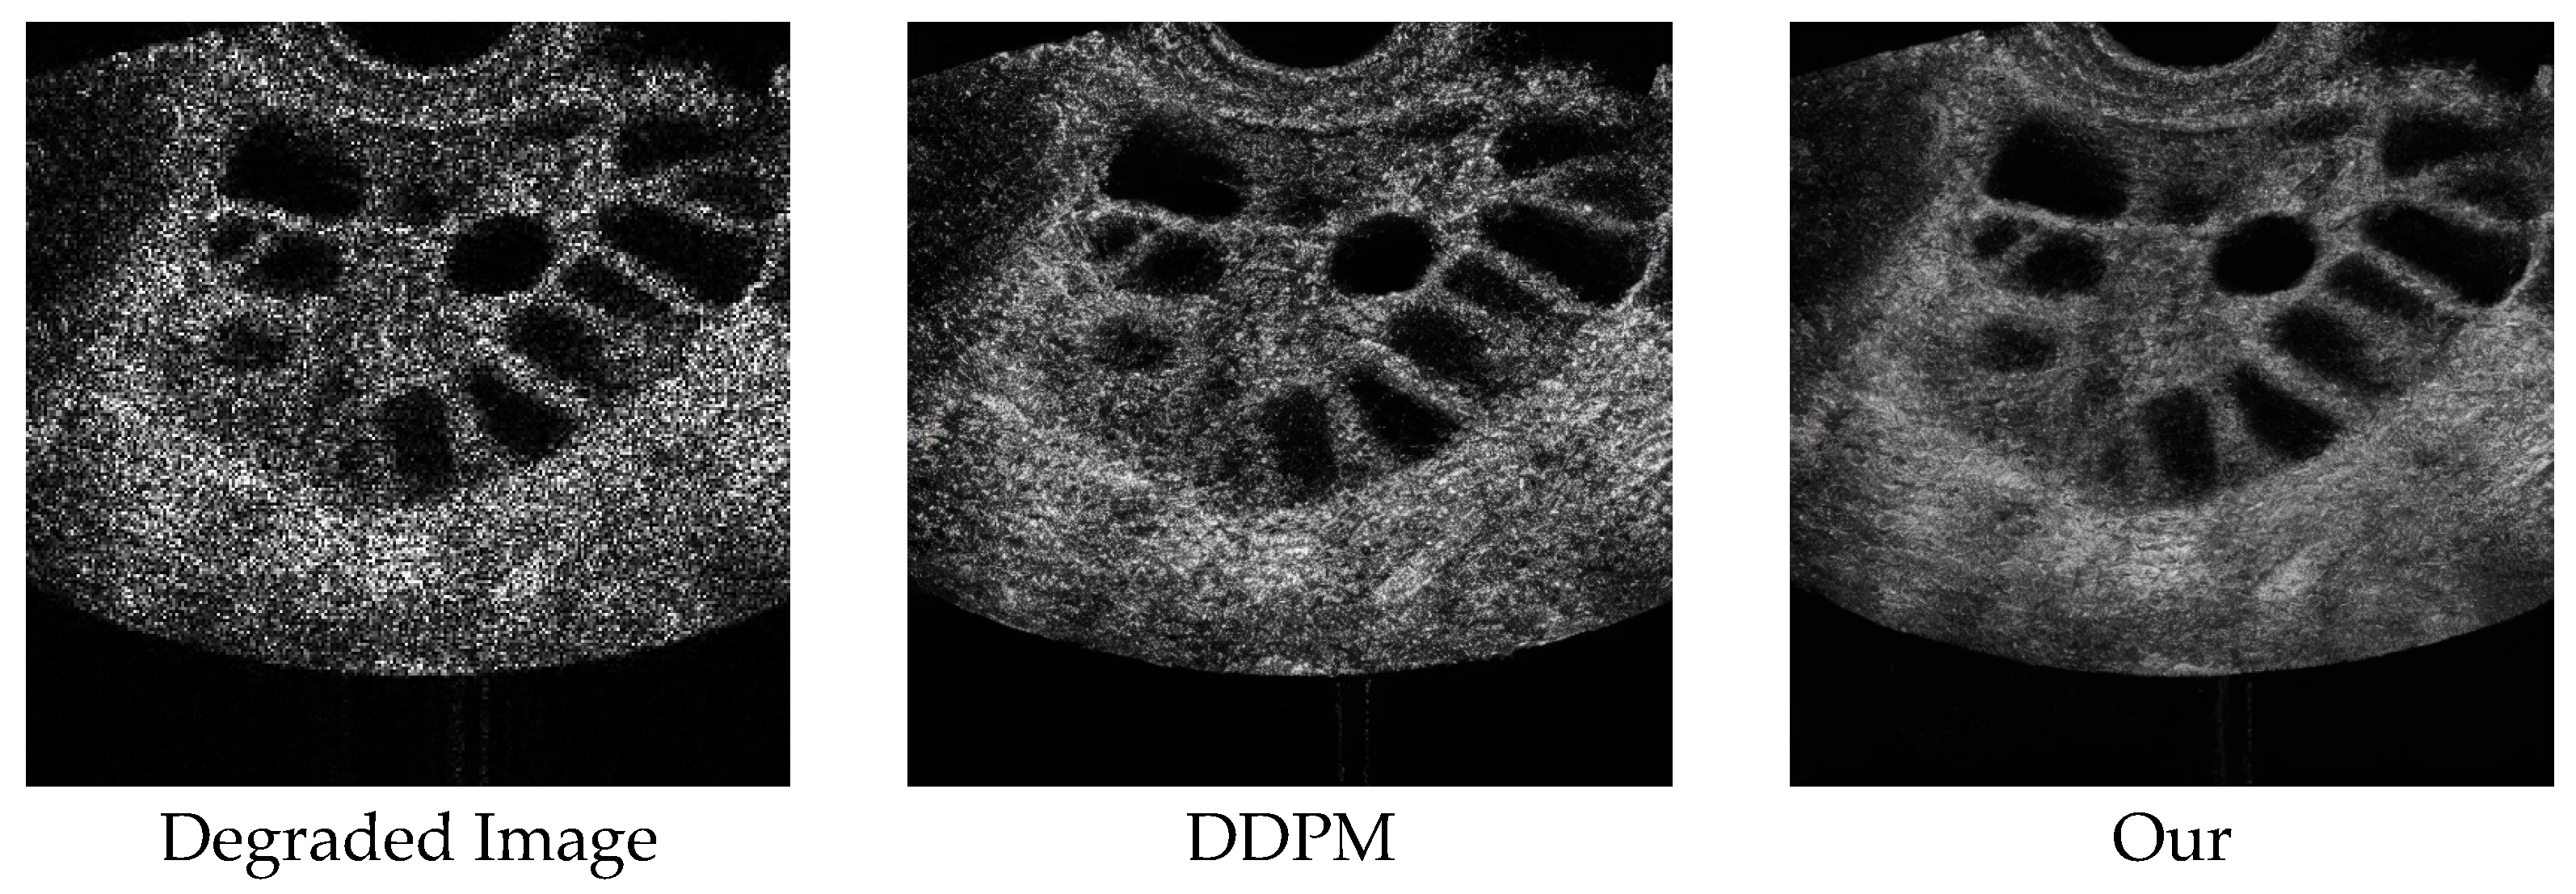

3. Results

| DDPM | 1000 | 28.05 | 0.8254 | 90.9101 | 31 s | ** |

| Ours | 1000 | 29.62 | 0.8612 | 55.3037 | 18 s | ** |